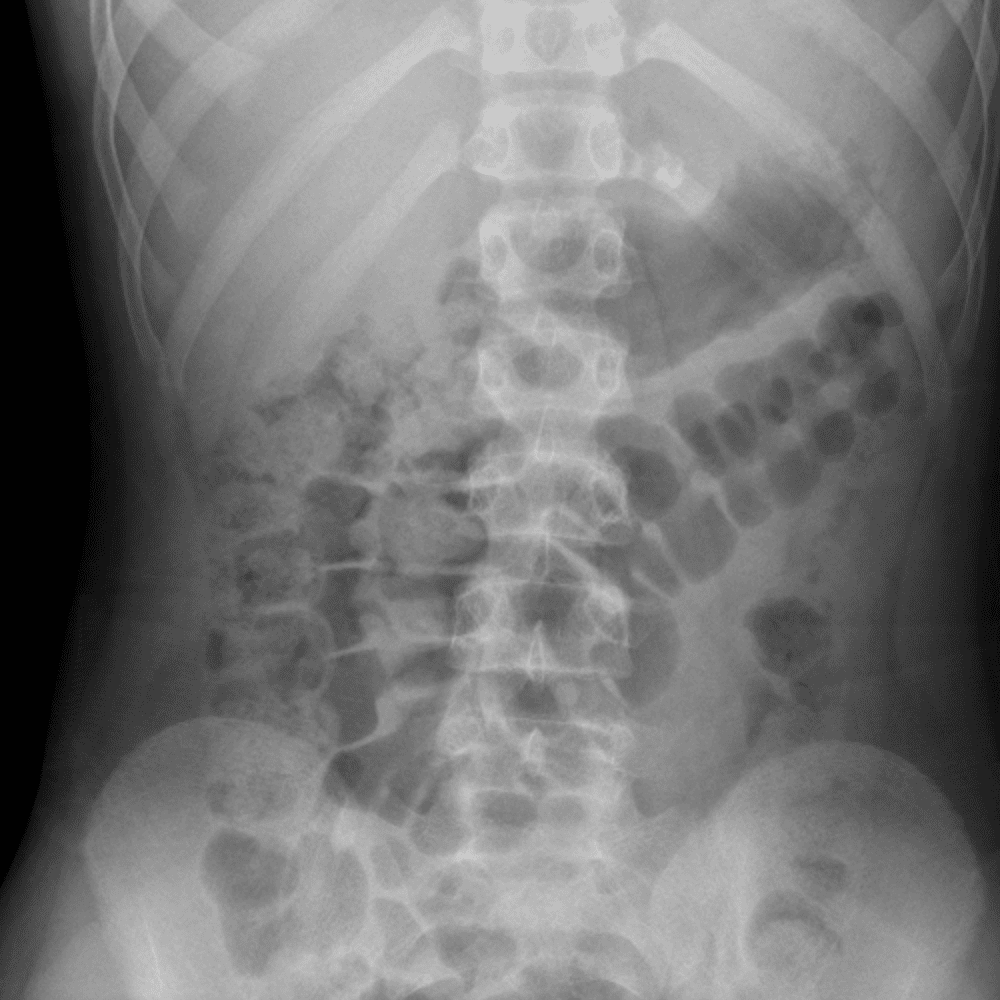

Peds Abdomen

Practice

Simulates call by including subtle or difficult cases and some normals.

30 cases